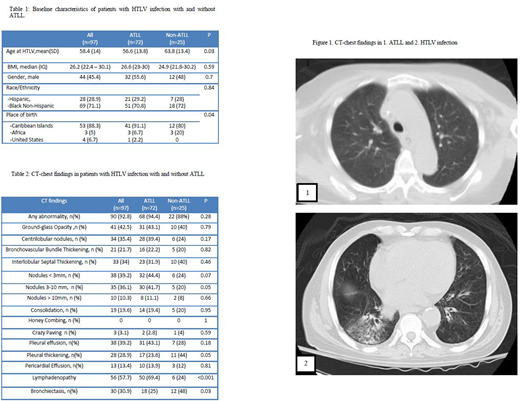

Among patients with ATLL, 52.1% had acute and 43.7% had lymphomatous types; while only 1.4% and 2.8% had smoldering and chronic type. The most common CT chest findings were lymphadenopathy (50, 69.4%); followed by 3-10 mm nodules (32, 44.4%), ground-glass opacity, pleural effusion (31, 43.1% each), centrilobular nodules (28, 39.4%), thickening of interlobular septum (23, 31.9%) and bronchiectasis (18, 25%). Compared to the acute subtype, patients with lymphomatous subtype had higher rates of lymphadenopathy (83.9% vs 64.9, p=0.07) and lower rates of bronchiectasis (16.1% vs 35.1%, p=0.07).

Among patients with non-ATLL, HTLV infection was diagnosed at an older age (63.8 vs. 56.6 years, p=0.03); HTLV-associated comorbidities were found in 16 cases (64%). Of these, myelopathy was the most frequent (10, 40%), followed by strongyloides (4, 16%). After HTLV diagnosis, CT chest was indicated in 28% patients for otherwise unexplained respiratory symptoms and to evaluate lung nodules or other chest X-ray abnormalities in 24% of cases. Bronchiectasis was the most common finding (12, 48%) followed by pleural thickening (11, 44%), ground-glass opacity and thickening of interlobular septum (10, 40%, each). Persistent abnormalities on follow-up imaging were present in 86.7% of the cases. Among patients with HTLV infection, those with ATLL were more likely to have nodules and lymphadenopathy (41.7% vs 20%, p=0.05 and 69.4% vs 24%, p<0.001, respectively) while bronchiectasis and pleural thickening was more likely in patients without ATLL (48% vs 25%, p=0.03 and 44% vs 23.6%, p=0.05; respectively).

Conclusions: Pulmonary findings are highly prevalent in CT chest of patients with HTLV infection with and without ATLL. Bronchiectasis and pleural thickening was more frequently encountered in non-ATLL patients while lymphadenopathy and nodules were common finding in patients with ATLL. Pulmonary involvement in lymphoma is usually characterized by nodules and lymphadenopathy but patients with ATLL had a higher incidence of findings including ground glass opacities, bronchiectasis and interlobular septal thickening possibly due to their underlying HTLV infection. Based on this data, nodules and lymphadenopathy should be classified as ATLL involvement of the lung while other findings described here could be due to HTLV infection. These findings are important in staging and response criteria for ATLL.